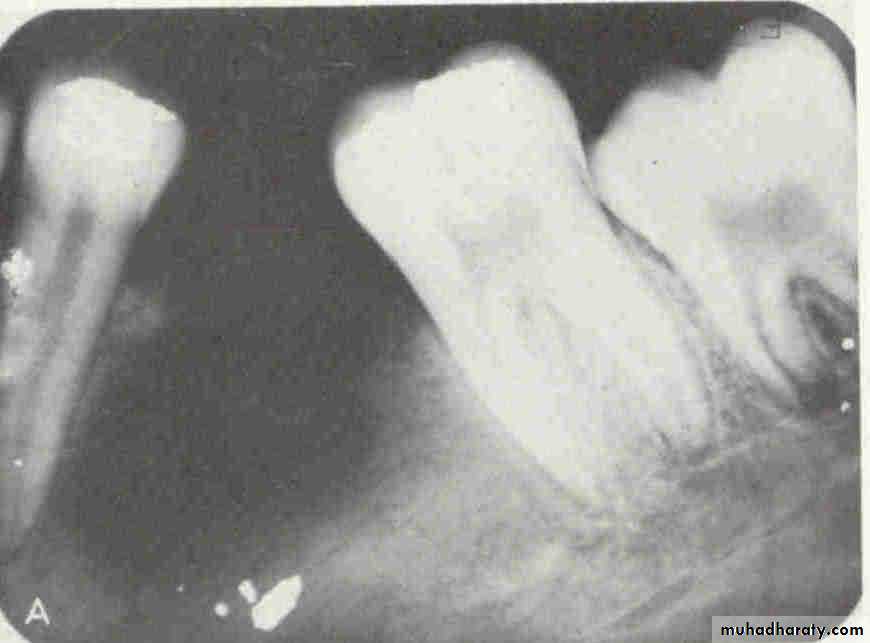

premolar filmThe arrow in the canine film is pointing to the gutta percha in which canal of the maxillary first premolar?

2

The arrow identifies the lingual canal. The tube head moves mesially from the premolar film to the canine film (beam directed more distally) and the gutta percha indicated by the arrow also moves mesially. (See following slide).

buccalWhen the tube head is moved mesially, with the beam directed distally, the two canals, which are initially superimposed (premolar periapical above) will separate. The lingual canal (red arrow) will follow the tube head movement and the buccal canal (blue arrow) will move in the opposite direction, as seen on the canine film.